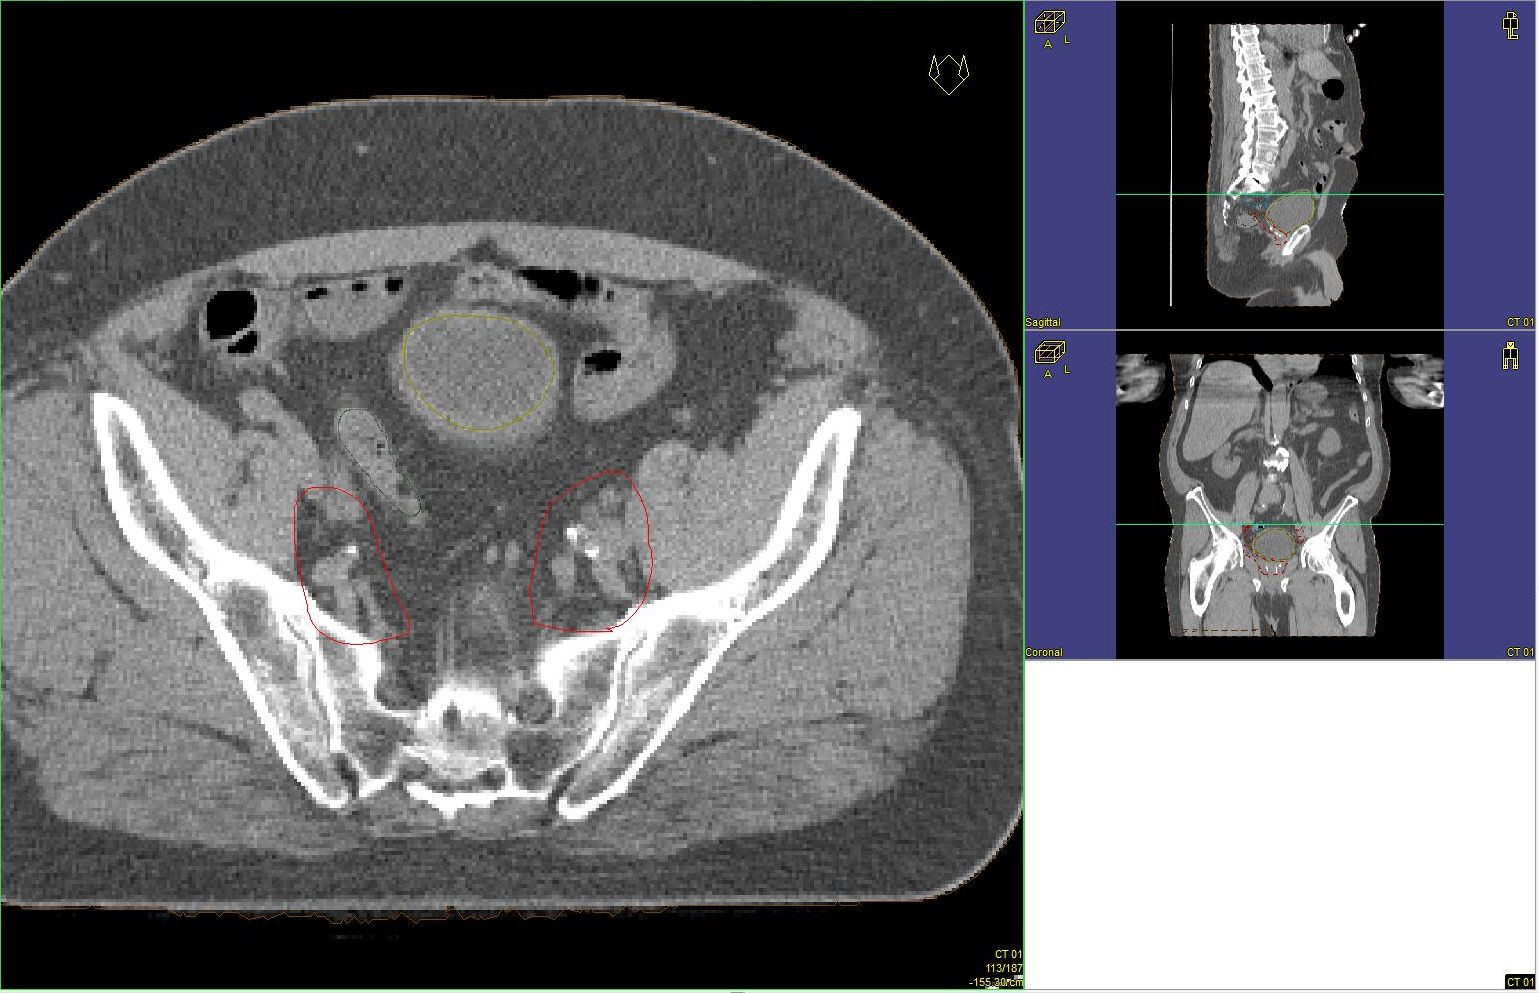

Prostata-Ca: Zielvolumen der postoperativen Radiotherapie

Beispiel: postoperative RT